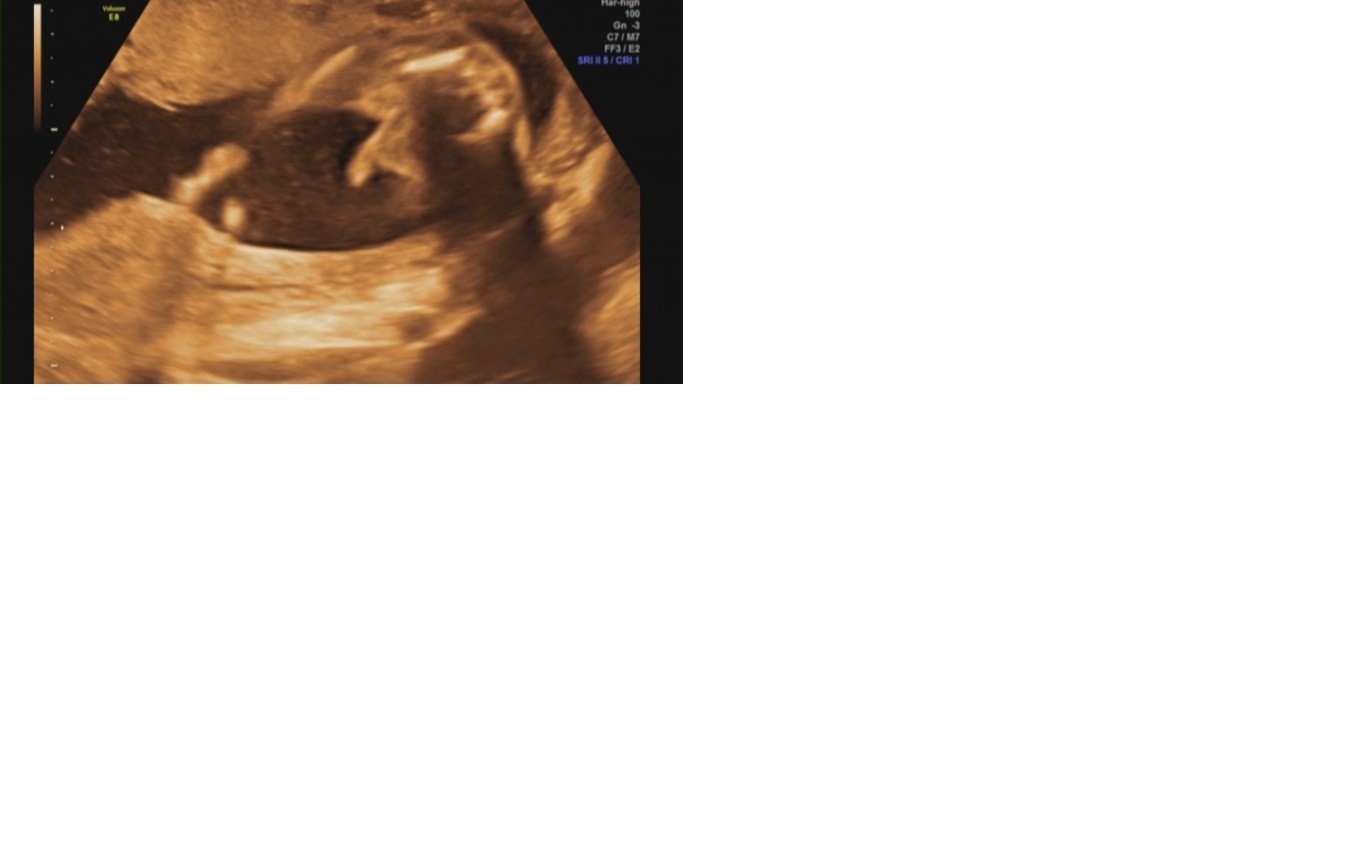

Agucha piekny Jas